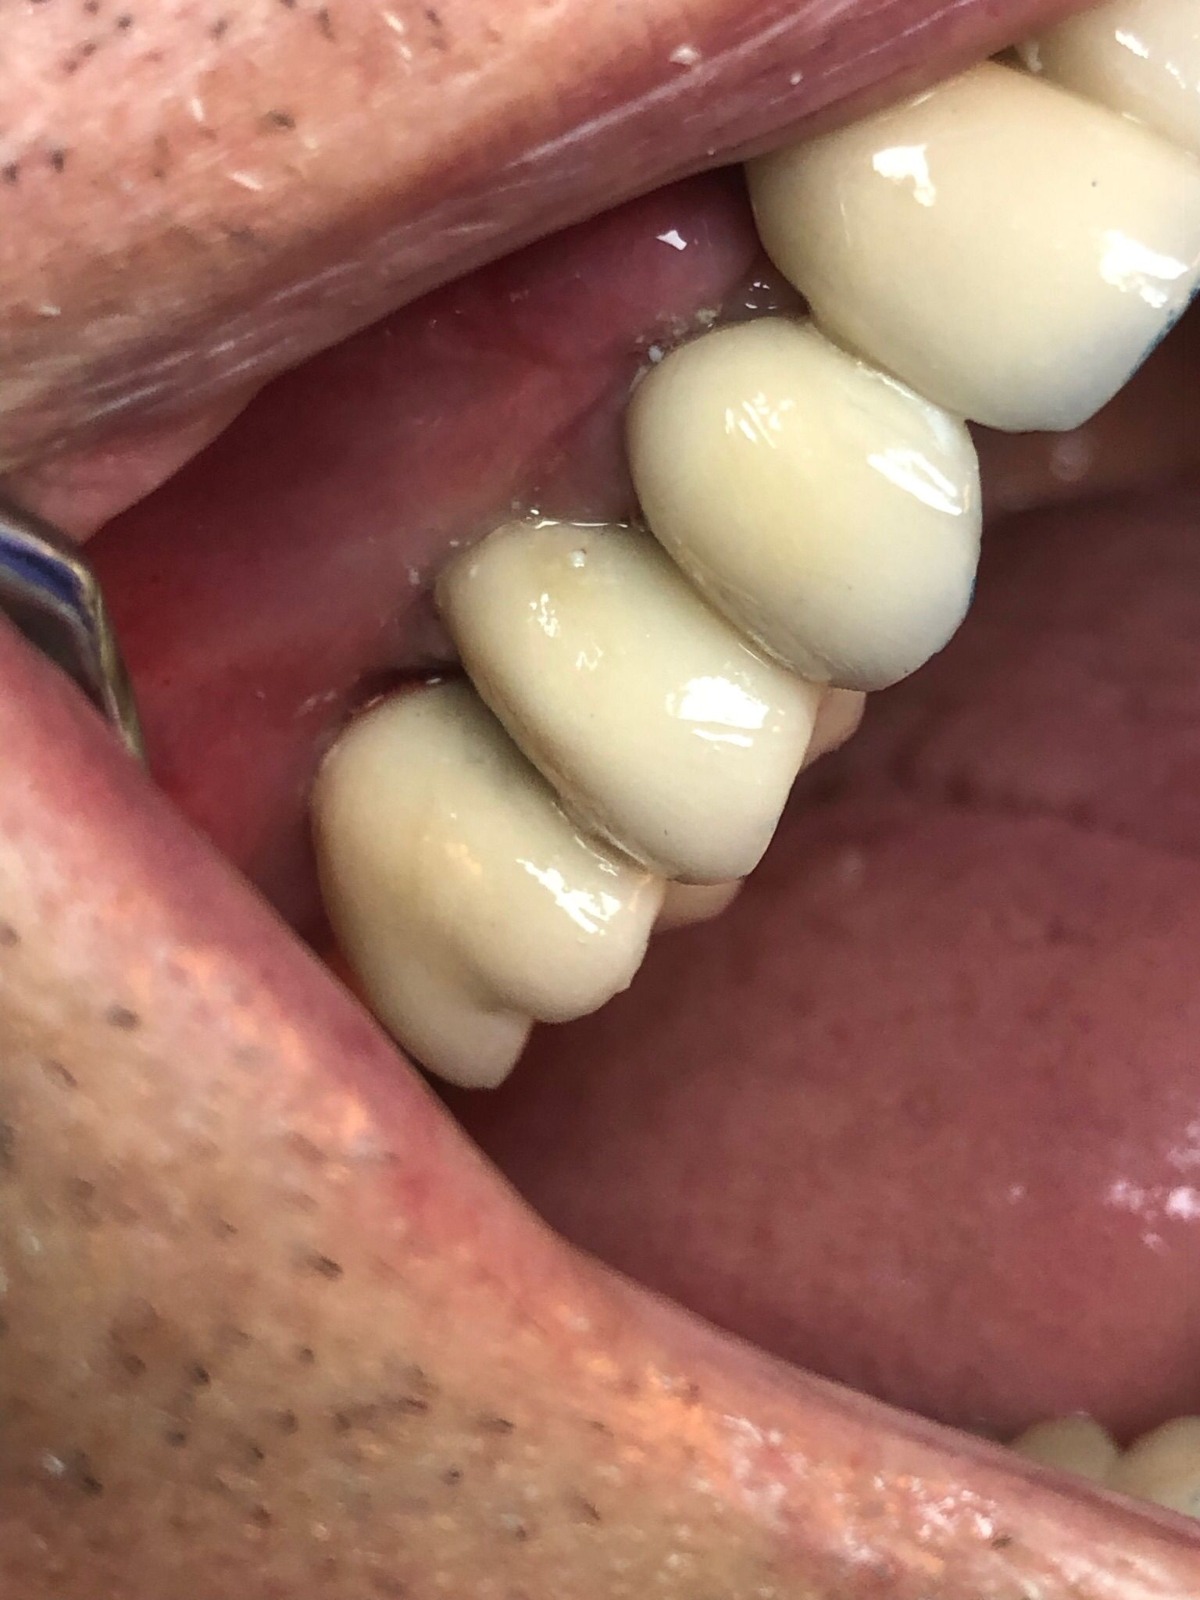

Actualmente vuelve el paciente de nuevo con la misma prótesis. Había roto dos de los tres pilares en concreto los más distales. El primero de los dos había roto la rosca del aditamento dentro del implante como ocurre habitualmente. Pero el ultimo pilar había roto directamente la cabeza del implante tal como se ve en la radiografía y lo que quedaba era un cilindro de titanio macizo perfectamente integrado en el maxilar, sin posibilidad de enroscar nada. Le explicamos al paciente que habría que quitar y poner un implante en el mismo acto. El paciente dijo que no, así que decimos que no se haría cirugía. Buscamos solución alternativa: hacemos un un agujero en el centro del macizo cilíndrico del implante roto y pasamos sucesivamente el set de machos roscantes. Utilizamos una fresa cañón de 1 mm que poco a poco se va introduciendo hasta 8mm con un poco de vagación, que hace que sea un poco mas de 1mm de diámetro. Posteriormente pasamos el conjunto de machos roscantes de métrica 2mm para poder usar un aditamento experimental, que era un palo de rosca de diámetro 2 mm unido a un cuerpo metálico en forma de sombrero napoleónico fabricado en cromo/cobalto, prototipos primitivos de la sistemática ASATIM y que tienen la característica de tener gran resistencia a la fractura. Nos llevó un tiempo largo el tallado de dichos aditamentos, tal como se puede observar en las imágenes, y tras cicatrizar la encía se le hizo una prótesis estándar. Esperemos que no lo rompa más veces.